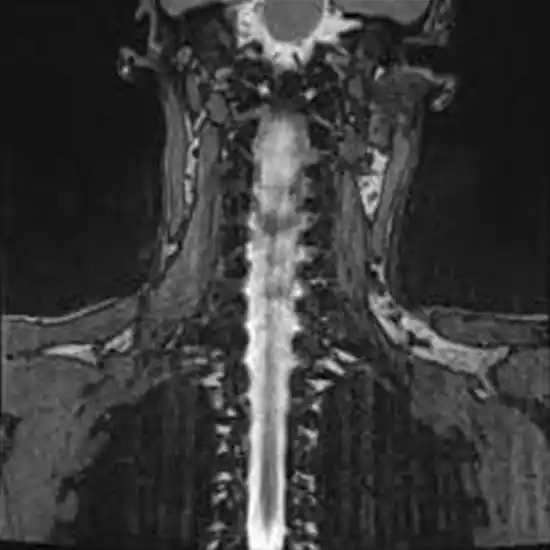

MRI Spine Myelography

MRI Spine With MR Myelography

Myelography uses fluoroscopy, real-time X-ray, and an injection of contrast material to look at the spinal cord, nerve roots, and spinal lining (meninges). It is beneficial for checking the spine after surgery and determining if a disc isn't working right in people who can't get an MRI.

Myelograms detect changes or anomalies in the spinal cord, subarachnoid space, and other tissues. Myelograms examine numerous disorders, including:

• Herniated discs compress nerves and the spinal cord.

• Neurological tumours

• Infection/inflammation of spinal cord and brain tissues